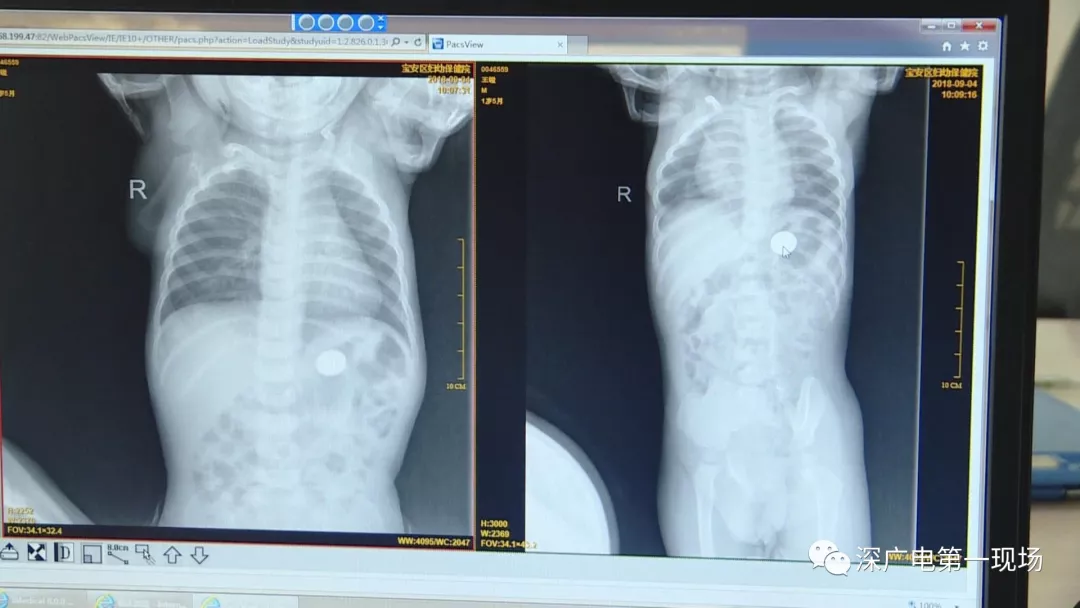

在術(shù)前檢查中

細(xì)心的醫(yī)生竟從

孩子的胸片中有了意外發(fā)現(xiàn)

9月4號(hào),一名1歲零5個(gè)月的男嬰因在家中摔傷,被父母送到了寶安區(qū)婦幼保健院,醫(yī)生診斷為左側(cè)尺橈骨骨折。在進(jìn)行全麻手術(shù)之前,院方例行對(duì)嬰兒進(jìn)行了周身檢查。手術(shù)前,兒外科醫(yī)生趙冠聰在查看患者的胸片時(shí),發(fā)現(xiàn)這名嬰兒的胃部有一枚硬幣大小的暗影。

胃部取出一角硬幣

已吞咽半月之久

經(jīng)過(guò)兩個(gè)小時(shí)的時(shí)間,兒科醫(yī)生郭景濤為患兒取出了藏在胃底的一角錢(qián)硬幣。目前,患兒已經(jīng)痊愈出院。